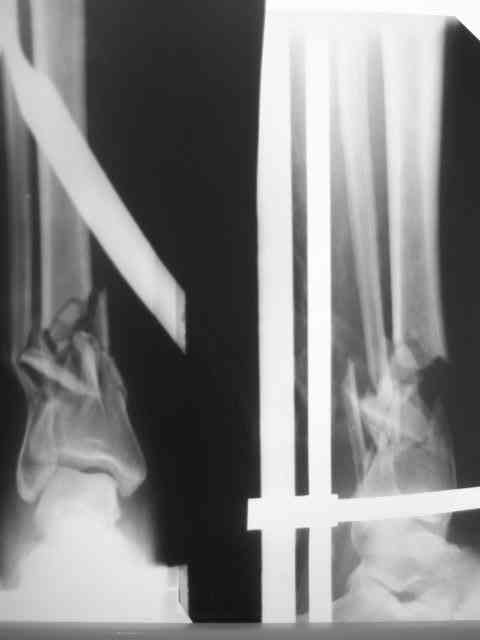

Здравствуйте коллеги! Вышел с отпуска и в палате оказалась данная

пациентка. Из истории выяснилось: травма 29.01.07 Диагноз: Открытый

оскольчатый перелом н/3 костей голени (якобы 2 Б Каплан), при

поступлении операция из трех букв и скелетное вытяжение + остальная

терапия. Затем выполнили остеосинтез штифтом (по ходу, Эксперт стоит)

видимо хотели  зацепится за дистальный отломок, но скорей всего все

было нестабильно и накинули этот  сокращенный АВФ. На сегодня (162

дня): Больная ходит с ограниченной нагрузкой на конечность  (трость).

Движения в г/стопе качательные. Трофика мягких тканей не

настораживает.  Воспаления м/тканей нет. В планах: 1. удаление штифта

2.Наложение стандартного АВФ с фиксацией стопы и устранение всех

смещений 3.Резекция нежизнеспособных костных отломков 4.Остеотомия в/3

большеберцовой кости с последующей дистракцией и замещением дефекта.